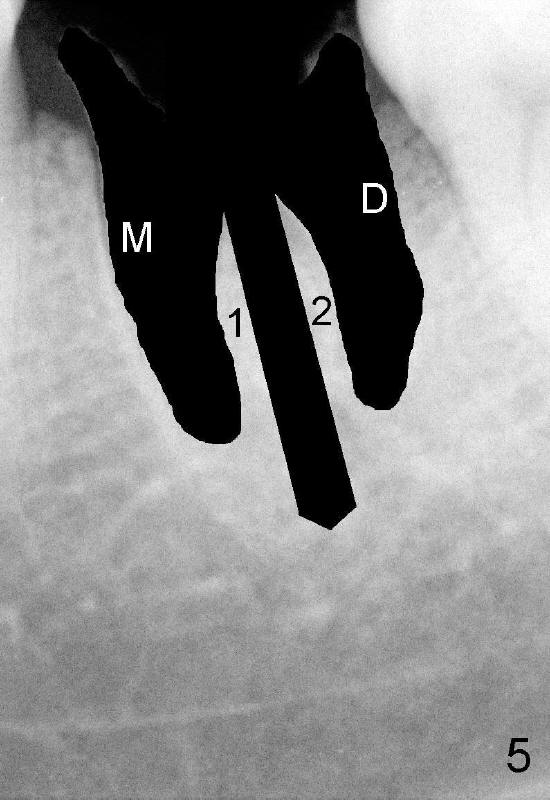

Instead, the roots are extracted (Fig.5). Using a variety of osteotomes (Fig.6: red) causes the mesial and distal segments of the septum (1,2) to be pushed into corresponding sockets (M,D).